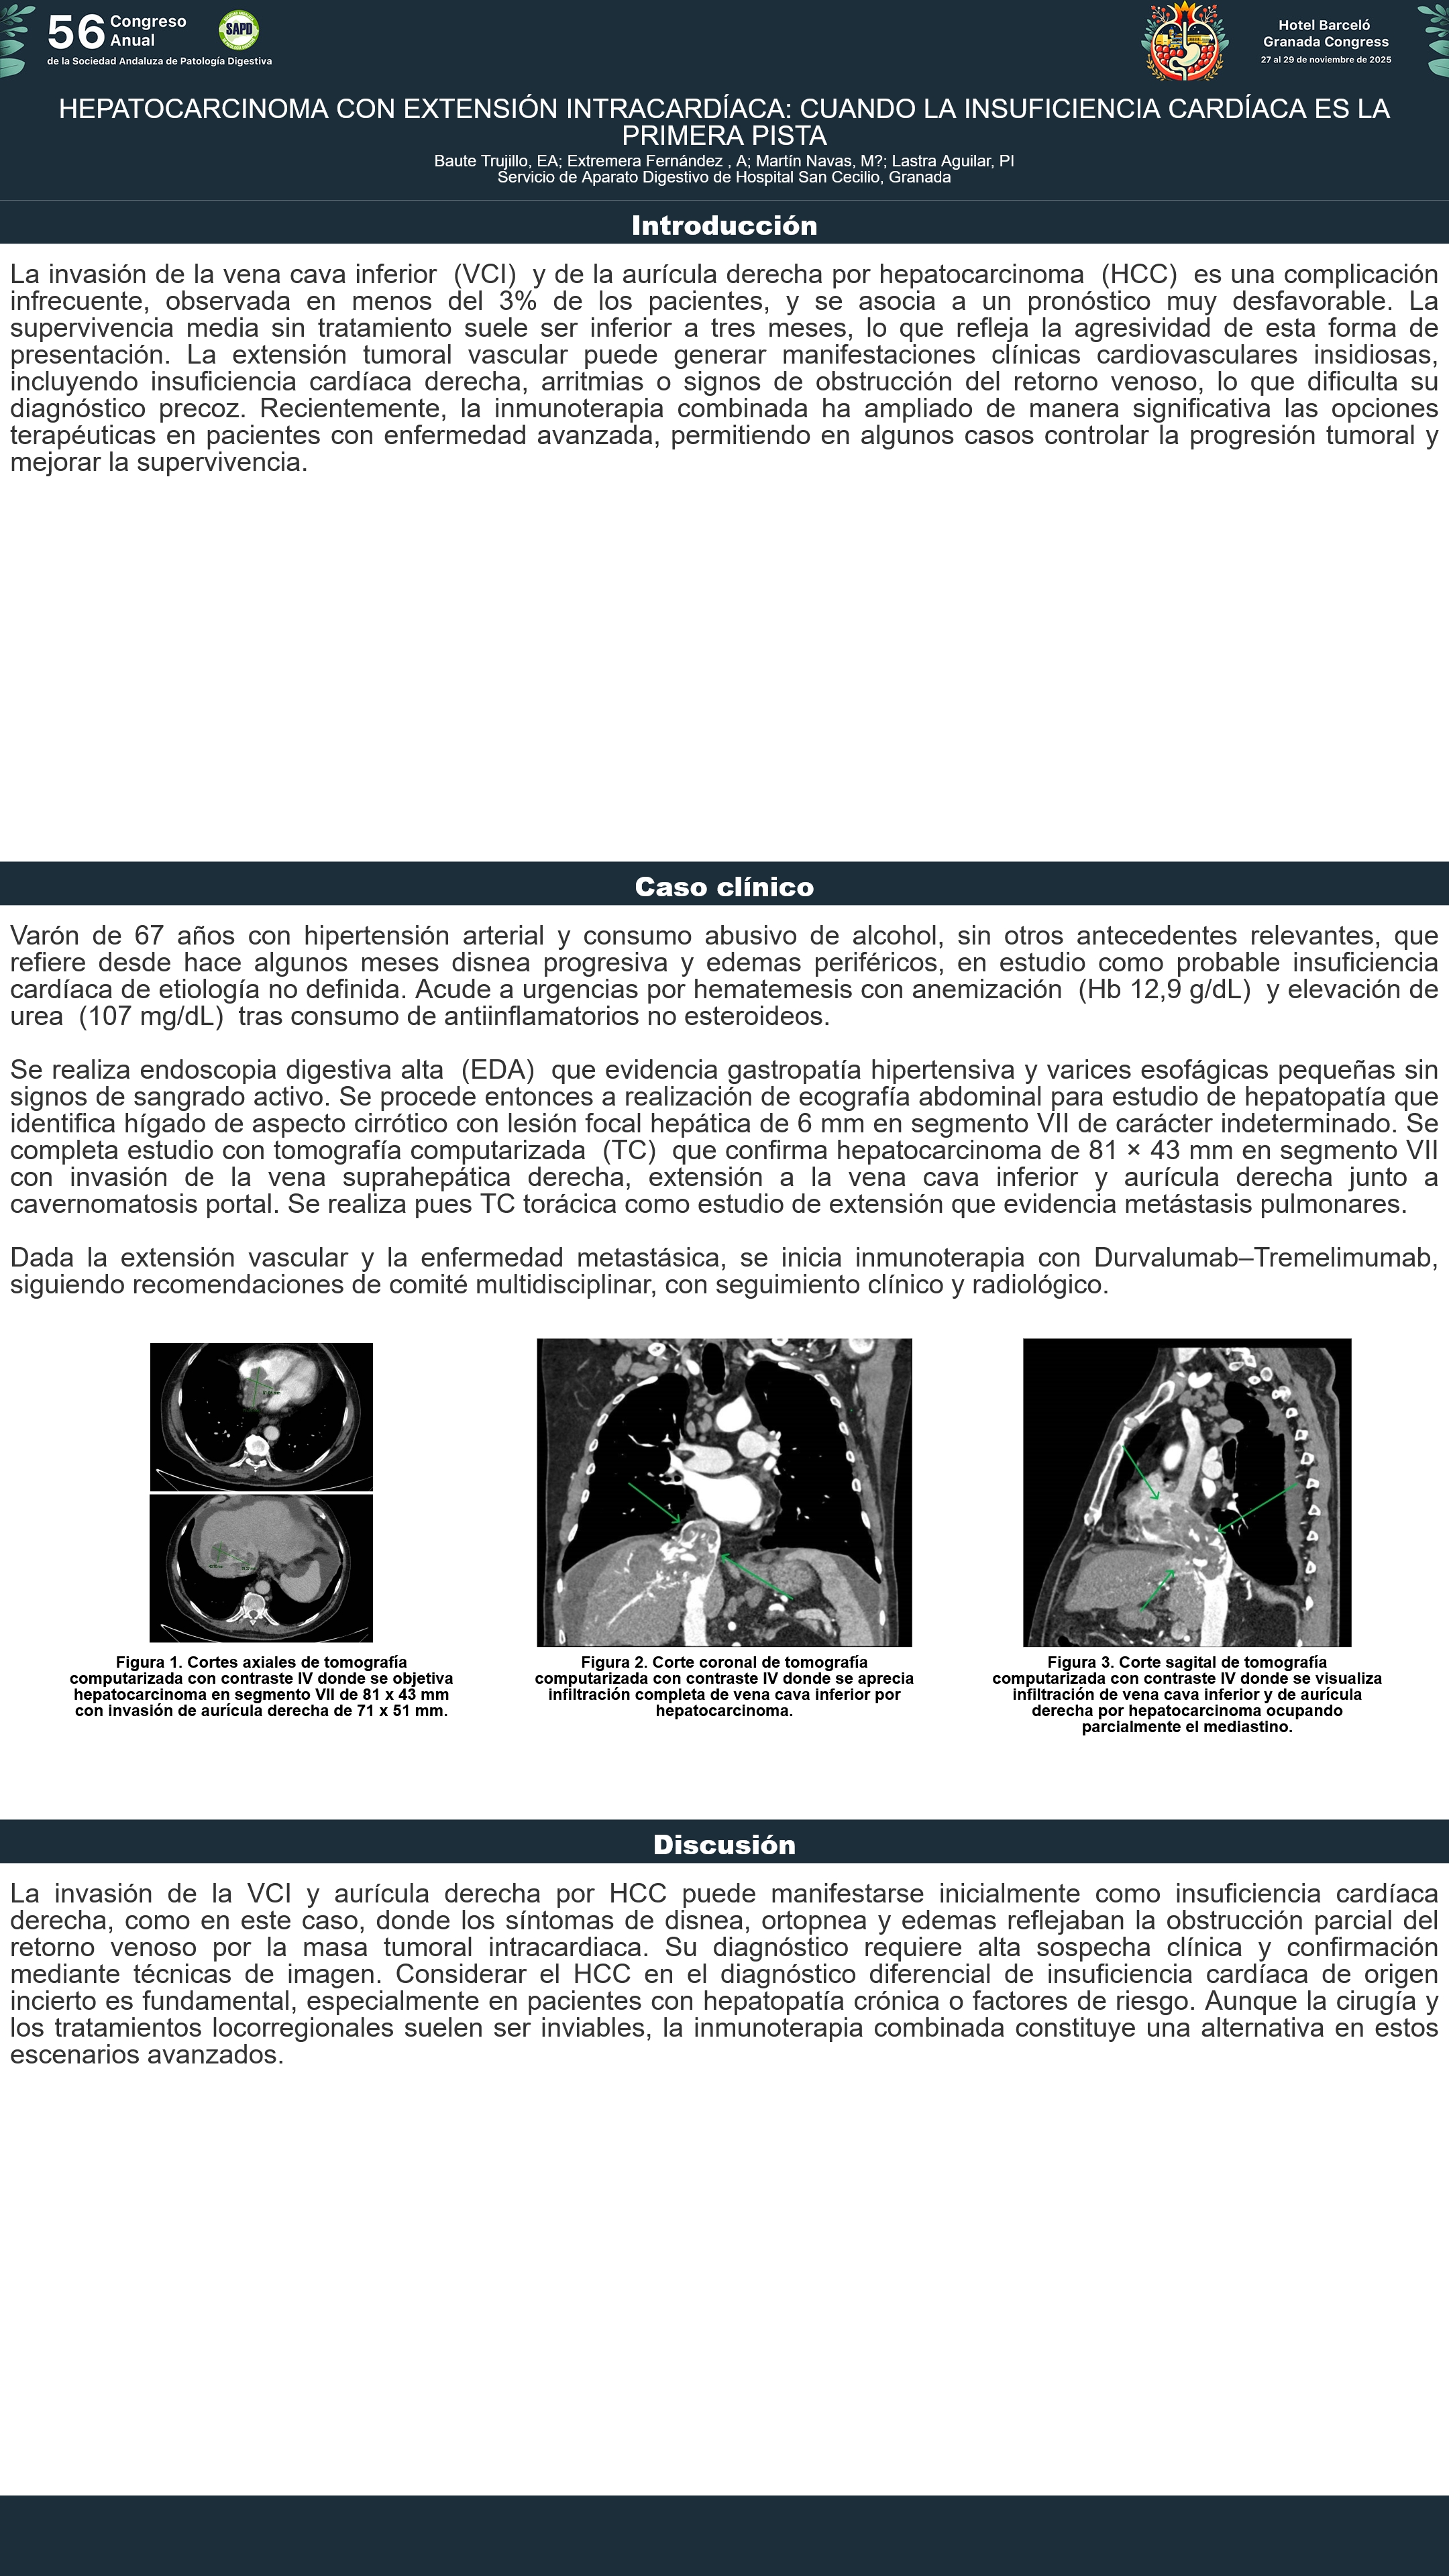

[CP-071] HEPATOCARCINOMA CON EXTENSIÓN INTRACARDÍACA: CUANDO LA INSUFICIENCIA CARDÍACA ES LA PRIMERA PISTA